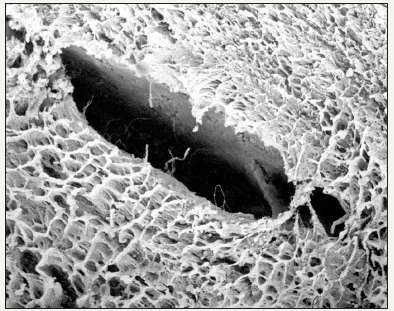

Figure 8:The porous structure of nucleus allows easily penetration of inflammatory cells and vascular coins that facilitate the comunication with lamellar disk arrangement.

The nucleus pulposus collected from discs classified as normal, appeared as a fibrillar substance arranged on an irregular pattern compared to the more organized annulus architecture that forms a sort of softer fibre weave. Inside the most internal area of discs classified as pathological, fibrils are organized to form a structure based on overlapping rows Figure 7 & 8. At higher resolution a fibrillar cribrous surface can be observed, indicating an identical presentation of collagen fibres. In some disc samples from patients over 70 years of age, it was possible to find spread microscopical areas arranged on a nodular pattern and formed by amorphous substances probably of amyloid nature [7].